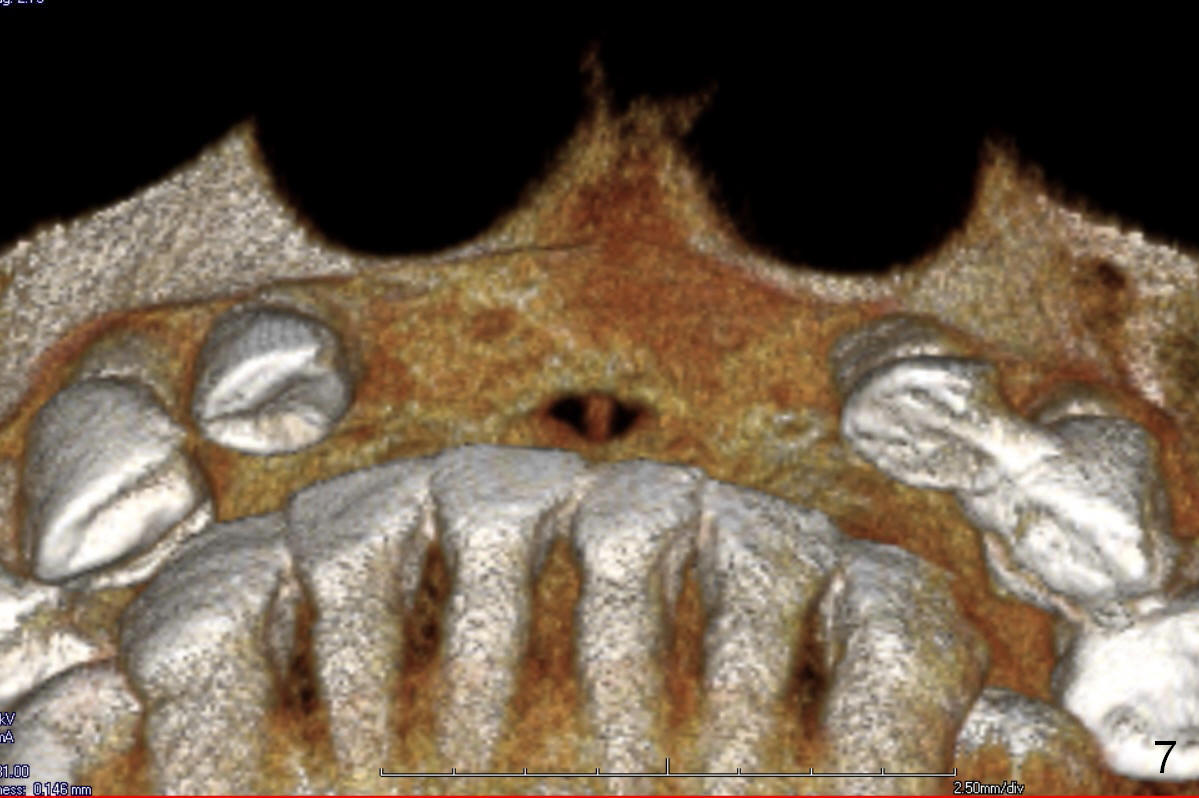

Since previous surgeries have demonstrated dense bone, bone expansion will be not used. Regular drills or reamers will be used for osteotomy. Pay attention to the Incisive Foramen while starting osteotomy (Fig.6,7).